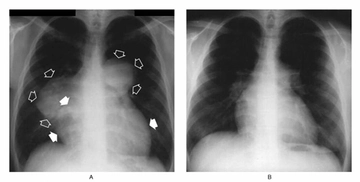

Temiz Akciğer Tomografisi Ne Anlama Geliyor?Günümüzde tıpta tanı ve tedavi süreçlerinde önemli bir yer tutan görüntüleme yöntemlerinden biri olan akciğer tomografisi, hastalıkların teşhisinde kritik bir rol oynamaktadır. "Temiz akciğer tomografisi" ifadesi, genellikle akciğerlerde herhangi bir anormal bulguya rastlanmadığı anlamına gelir. Bu bağlamda, temiz bir akciğer tomografisi sonucu, hastanın akciğer sağlığının iyi olduğunu gösterir. Akciğer Tomografisi Nedir?Akciğer tomografisi, yüksek çözünürlüklü görüntüler elde etmek için X-ray teknolojisini kullanan bir görüntüleme yöntemidir. Bu yöntem, akciğerlerin iç yapısının detaylı bir şekilde incelenmesine olanak tanır. Tomografi, akciğerlerdeki lezyonlar, tümörler, enfeksiyonlar ve diğer patolojilerin tespit edilmesinde son derece etkili bir yöntemdir. Temiz Akciğer Tomografisi SonucuTemiz bir akciğer tomografisi sonucu, şu durumları ifade edebilir: